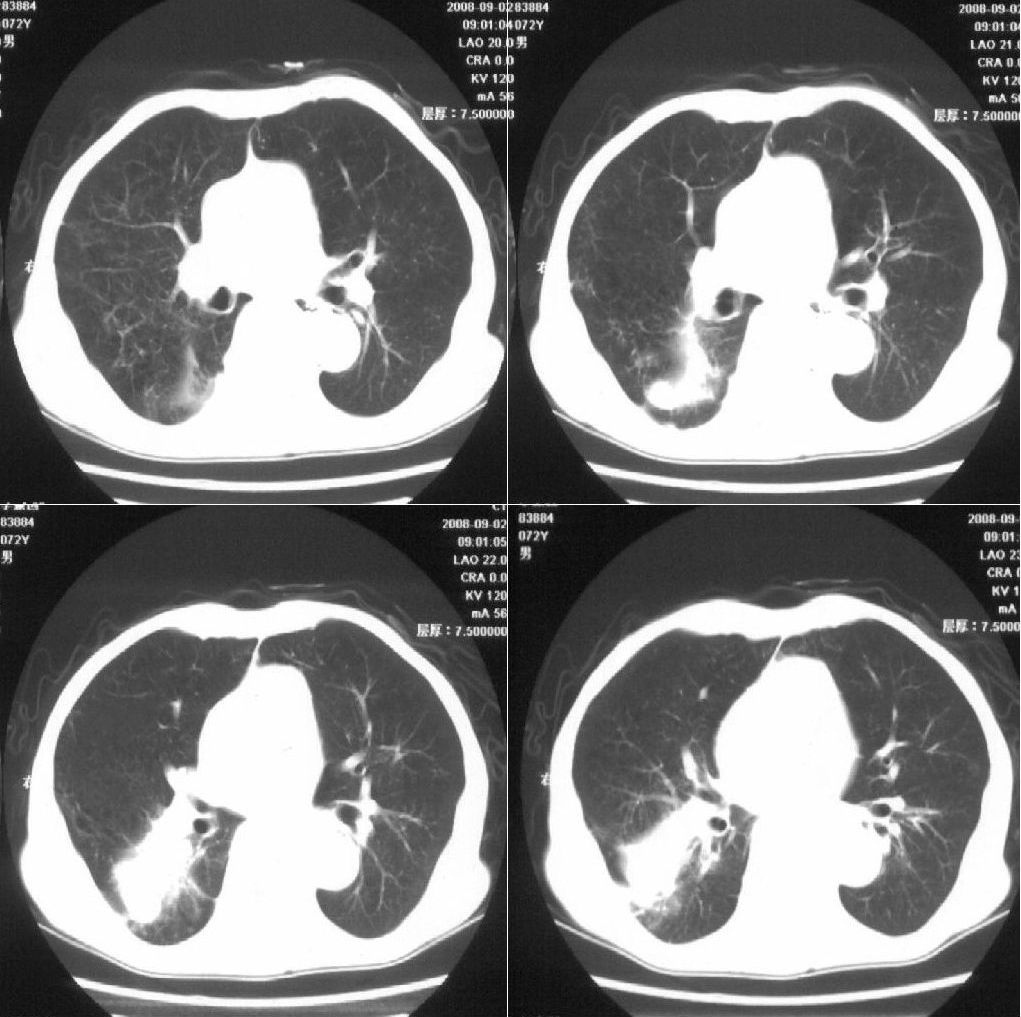

标题: 病例追踪

该患者通过抗炎治疗明显好转:当时患者消瘦,实是因为患者进食量不多。患者有食道癌,因发生原发肺癌的机率并不高,当时的ct片除了增强感觉有强化外(其实这信息也并不确定,因为是外院ct),其实并没有发现支气管腔改变等直接征象。经过治疗,患者现在一般情况良好。以下是9月22日的复查片,发现病灶吸收明显。纵隔窗就不上传了。

[本贴已被 fanshl 于 2008-9-26 10:52:11 修改过]